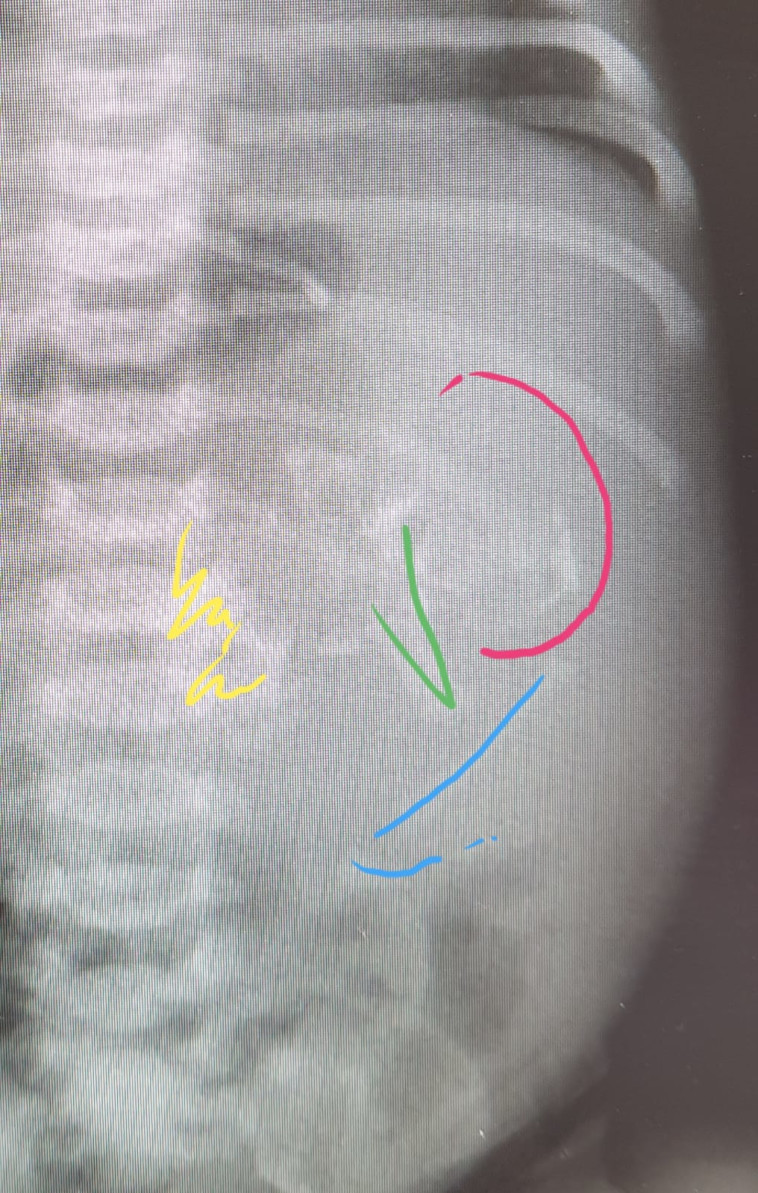

צילום הרנטגן בו נראה עובר בתוך בטנה של התינוקת

צילום הרנטגן בו נראה עובר בתוך בטנה של התינוקת | צילום: אסותא אשדוד

ד"ר עומר גלובוס, הרופא המטפל בפגיה, סיפר בשיחה עם "מעריב": "מדברים על אישה שכאשר הגיעה ללדת נכנסה והיה רושם שהתינוקת שבבטנה יש לה בטן גדולה. בעקבות זה - מיד לאחר הלידה בדקנו את התינוקת ושמנו לב שאנחנו מממששים משהו בתוך הבטן. לכן גם העברנו אותה בדיקות אולטרסאונד ועוד".

ד"ר גלובוס הסביר ממה יכול להתפתח מצב רפואי כזה. "זה יכול להיות הריון שהתחיל כתאומים ובשלב מסוים אחד התאומים נסגר על השני, במובן של איברים ולא בליעה דרך הפה. ההתפתחות כמובן נעצרה והעובר לא היה חי. זה תואר גם במקרים של אנשים בוגרים שעשו בירור כלשהו ופתאום גילו שיש להם עובר בבטן".

"התיאוריה השנייה היא שמדובר בגידול שפיר שמערב רקמות של חלקים בגוף. זה מקרה נדיר. רוב הרופאים בתחום שלי שמעו על מקרים כאלה אך מעטים בלבד ראו. התינוקת בריאה ושלמה", סיכם ד"ר גלובוס.